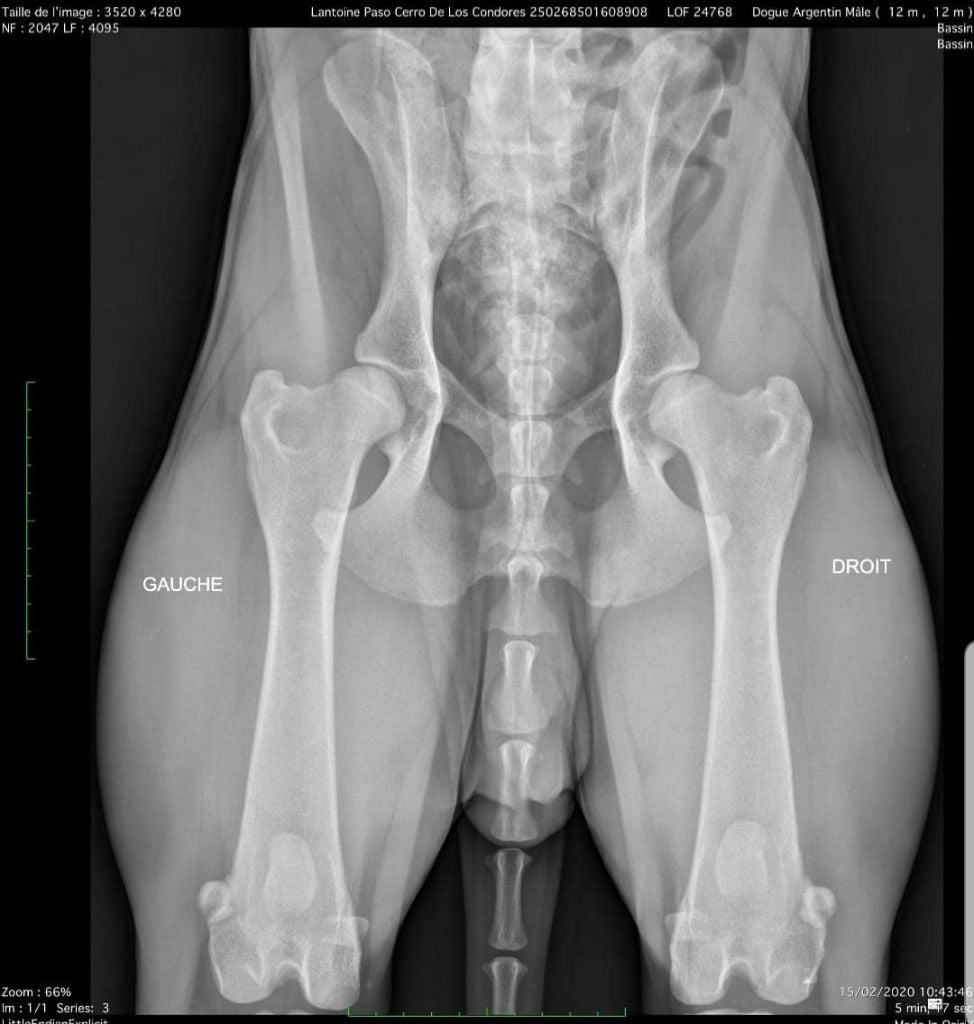

Dysplasie B/C (lecture non officielle, radio disponible).